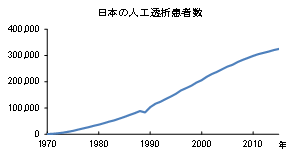

腎臓の細胞増殖を促進して機能を高めるD-アミノ酸(D-セリン)の新しい機能を発見

生体中に微量に存在し、加齢とともに変動するD-アミノ酸のひとつであるD-セリンに、腎臓の細胞増殖を促進して機能維持する作...

腎臓の細胞増殖を促進して機能を高めるD-アミノ酸(D-セリン)の新しい機能を発見

生体中に微量に存在し、加齢とともに変動するD-アミノ酸のひとつであるD-セリンに、腎臓の細胞増殖を促進して機能維持する作...